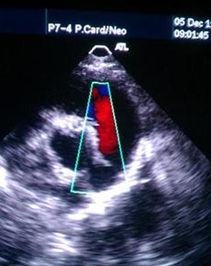

頸動脈彩超 頸動脈彩超不僅能清晰顯示血管內中膜是否增厚、有無斑塊形成、斑塊形成的部位、大小、是否有血管狹窄及狹窄程度、有無閉塞等詳細情況,並能進行準確的測量及定位,還能對檢測動脈的血流動力學結果進行分析。特別是可檢測早期頸動脈粥樣硬化病變的存在,使患者得到及時預防和治療;對中重度頸動脈狹窄和閉塞的及時確診,可作為臨床選用頸動脈內膜剝脫術治療的有力依據。

頸動脈彩超與TCD檢測技術聯合套用於臨床可以及時準確的觀察缺血性腦血管產生的顱內、外血流動力學變化,可以提高顱內、外腦血管疾病的檢出率和診斷正確率,為臨床選擇不同的治療方法和獲得有效的治療效果提供可靠的客觀的影像學和動力學依據。

頸動脈超聲檢查可為動脈粥樣硬化的診斷提供一種無創、簡便、重複性好的方法。但在檢測結果分析中應提倡多參數分析,除相關血管段流速外,還得考慮搏動指數,頻譜形態、血流方向和血流聲等。頸動脈超聲檢查有助於確定缺血性腦血管病患者頸動脈粥樣斑塊的性質和穩定性,確定頸動脈粥樣硬化及頸動脈狹窄的程度,尤其在顯示動脈壁結構的變化上有優勢,為動脈粥樣硬化的早期預防和治療提供客觀的依據,積極治療動脈粥樣硬化及頸動脈狹窄對預防缺血性腦卒中有重要意義。